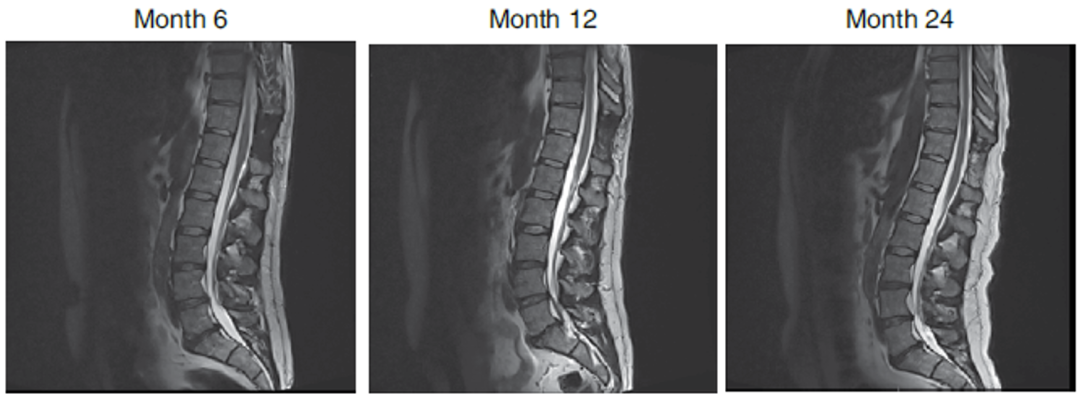

参与治疗的患者影像学结果显示无异常

这项临床试验的主要目的是证明将CNS10-NPC-GDNF注射到脊髓中不会产生安全问题,并且不会对患者的腿部运动功能产生负面影响。